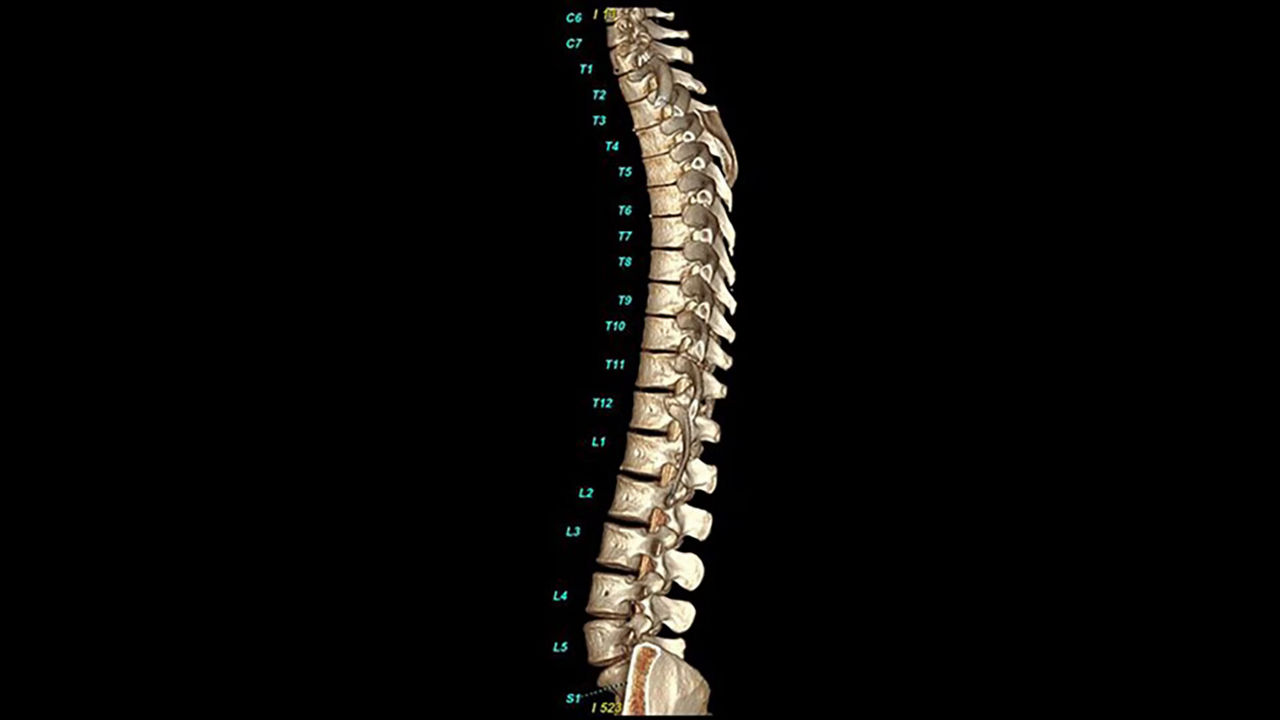

<p>Spine Auto Views</p>

Learn more

<p>Bone VCAR</p>